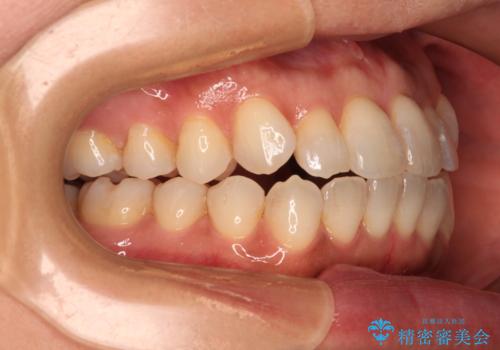

前歯のクロスバイト インビザラインによる矯正治療

インビザライン特有の、治療後半に奥歯が咬み合わないという事象が長引きました。

咬み合わないときの対処方法は色々とありますが、ゴムかけなどを活用して噛めるようにしました。